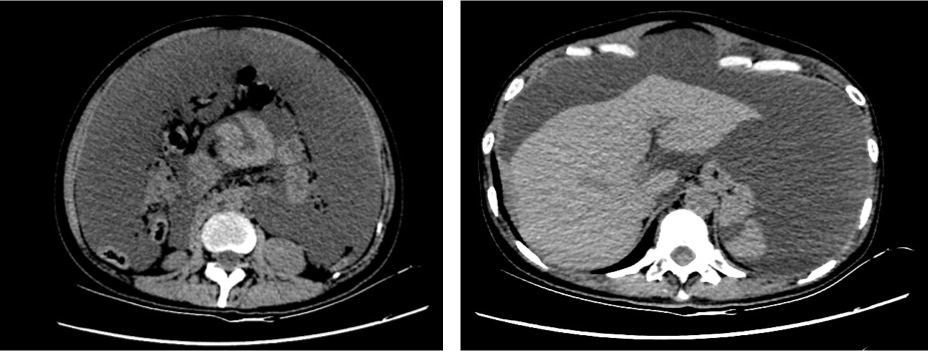

腹部CT:肝右叶S6~8肝包膜下多发结节,考虑转移瘤;肝右叶包膜局部不均匀增厚,右上腹腹膜结节状增厚,上腹部胃小弯侧多发结节,考虑腹腔种植转移;子宫后上方一不规则、多房、囊实性肿块,考虑双侧卵巢恶性肿瘤,囊腺癌可能;子宫前方肿块,考虑腹膜种植转移可能;腹膜后未见明显肿大淋巴结;大量腹水(图1)。

图1. 患者的腹部CT结果

影像学诊断:双侧卵巢高级别浆液性癌伴腹膜网膜多发转移,盆腔转移,腹盆腔积液。腹膜后未见明显肿大淋巴结。